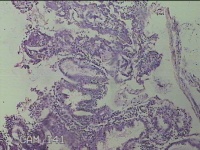

性别

女

年龄

51岁

临床诊断

子宫多发性肌瘤 宫颈多发赘生物 宫颈息肉 子宫异常出血

一般病史

阴道断续流血数月余。

标本名称

宫腔内膜

大体所见

灰白暗红色不规则碎组织5.5x4.3x0.3cm一堆。

子宫内膜腺体呈分泌改变。